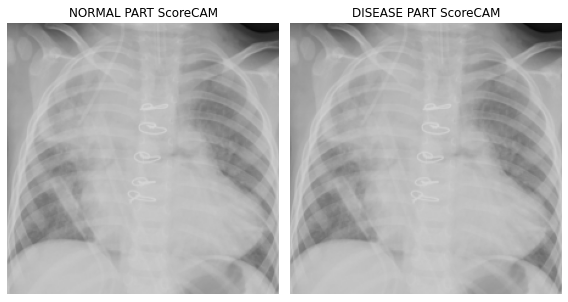

fig, (ax1,ax2) = plt.subplots(1,2)

dls.train.decode((x,))[0].squeeze().show(ax=ax1)

ax1.imshow(-cam_scorecam.squeeze(),alpha=0.5,extent=(0,224,224,0),interpolation='bilinear',cmap='cool')

ax1.set_title("NORMAL PART ScoreCAM")

#

dls.train.decode((x,))[0].squeeze().show(ax=ax2)

ax2.imshow(cam_scorecam.squeeze(),alpha=0.5,extent=(0,224,224,0),interpolation='bilinear',cmap='cool')

ax2.set_title("DISEASE PART ScoreCAM")

fig.set_figwidth(8)

fig.set_figheight(8)

fig.tight_layout()